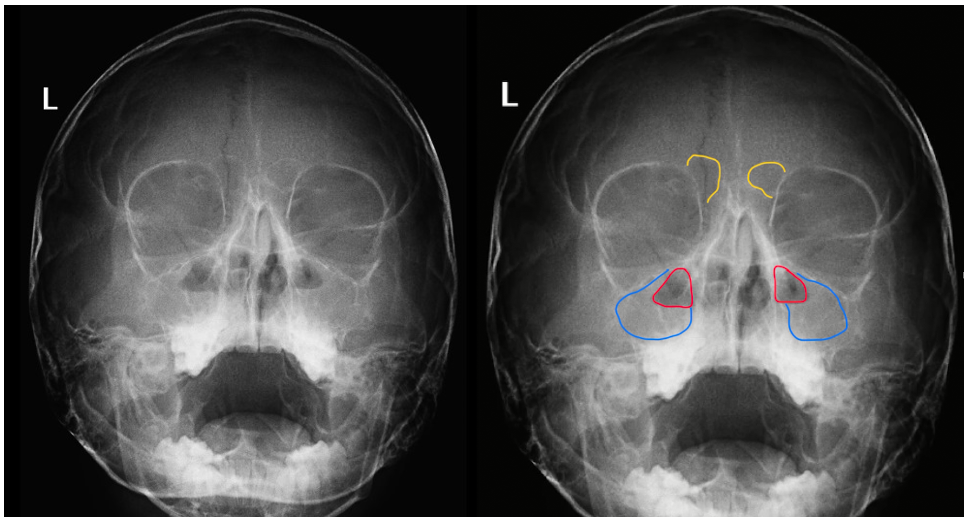

Например на этом снимке. Мы оцениваем воздушность пазух и определяем неодинаковость верхнечелюстных пазух, рисуем их контур и видим что с одной из сторон он слишком рано обрывается, а остальная часть пазухи является более светлой (выделено синим). Это и есть наша воспалительная жидкость. Только что мы диагностировали односторонний гайморит.